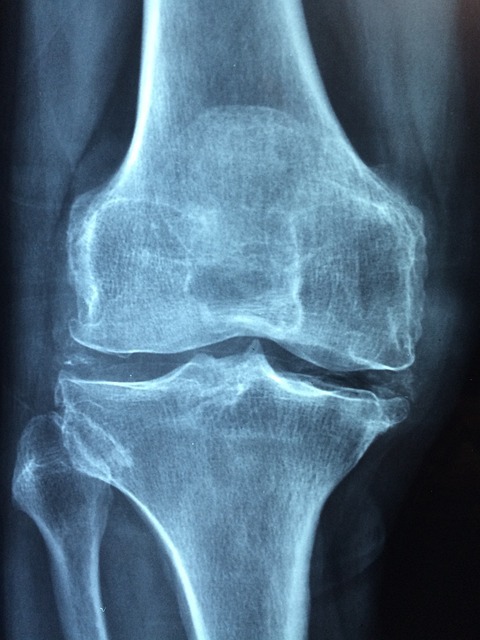

인종과 지역을 막론하고 가장 흔한 질병 중 하나인 "퇴행성 관절염"에 대한 아로마테라피의 효과에 관해 이야기해 보려고 합니다. 연골의 퇴행성 변화와 관절 주변에서의 역학적 유전적인 요인으로 발생하는 이 질환은 아로마테라피를 통해 관리할 수 있는 방법을 함께 알아보겠습니다.

- 퇴행성 관절염은 손가락, 무릎, 발가락, 경추, 요추와 같은 다양한 관절에 발생하는 만성적인 질환입니다.

- 연골의 퇴행성 변화와 관절 주변의 역학적 유전적인 요인이 결합하여 발생합니다.

- 원발성 관절염과 2 차성 관절염으로 구분되며 과도한 사용, 급성 골절, 갑상선 기능 항진증, 신경질환 등이 2 차성 관절염의 원인이 될 수 있습니다.